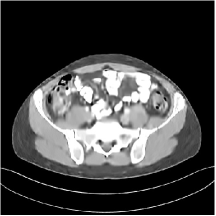

III.C. Low-dose Experiments with Mayo Clinic Data

First, we study transform training based on Mayo Clinic data. As shown in Fig. 6, seven slices obtained at regular dose from three patients are used for transform learning. The number of pixels . Similar to the phantom experiments, overlapping patches are extracted with a patch stride. The number of overall training patches is about . We set for ST, , , for MARS2, , , , , for MARS3, , , , , , , , , for MARS5, , , , , , , , , , , , , for MARS7. The iteration number in Algorithm 1. Fig. 7 illustrates the learned transforms obtained with Mayo Clinic data. Different from the XCAT phantom case, these transforms up to MARS5 display more complex features and structures. The rich features of the MARS models better sparsify the training images over layers compared to the single-layer model (ST).

III.C.2. Simulation Framework, Reconstruction Results, and Comparisons

The synthesized low-dose clinical measurements are simulated from regular-dose images at a resolution of mm with a fan-beam CT geometry corresponding to a monoenergetic source at incident photon intensity . The sinograms are of size . The width of each detector column is mm, the source to detector distance is mm, and the source to rotation center distance is mm. We reconstruct images of size with the pixel size being mm mm.

We conducted experiments on one test slice used for parameter tuning (L067-slice 120) and four independent test slices (L109-slice 90, L192-slice90, L333-slice140, L506-slice 100) of the Mayo Clinic data. For PWLS-EP, we ran iterations using relaxed OS-LALM and set regularization parameter . We used the same as the phantom experiments for Algorithm 2. The process of selecting a general set of reconstruction parameters () for the Mayo Clinic test slices is identical to that for the XCAT phantom in Section III.B.2. The selected regularization parameter and the parameters that control the sparsity of the coefficient maps are for ST, , , , , for MARS2, , , , , , , for MARS3, , , , , , , , , , , for MARS5, and , , , , , , , , , , , , , , for MARS7, respectively.

Figs. 8, 9, 10, and 11 show the reconstructions of the four independent slices using the FBP, PWLS-EP, PWLS-ST, PWLS-MARS2, PWLS-MARS3, PWLS-MARS5, and PWLS-MARS7 schemes, respectively. Additional Mayo Clinic experimental results of the parameter tuning case (Fig. 15) are shown in the supplementary document. Table 1 lists the RMSE and SSIM values of reconstructions of the four independent test slices, with the best values bolded. Generally, the five and seven layer models provided the best RMSE and SSIM values. They outperform the single-layer model by HU in RMSE on average. However, the MARS5 and MARS7 models perform similarly. In order to strengthen the benefits of the multi-layer model, Table 2 lists the RMSE of the reconstructions in four different ROIs (shown in the reference of Fig. 11) with seven methods for slice 100 of patient L506. By observing the reconstructed images, we see that although the ST model achieves a cleaner reconstruction result than FBP and PWLS-EP, it still sacrifices some sharpness of the central region and suffers from loss of details. The deeper models have a somewhat more positive effect in terms of maintaining subtle features, which is clearly more essential to clinical diagnosis. Furthermore, as we will discuss later, after considerable parameter tuning, we found that the information contained in residual maps is gradually decreased with the number of layers, eventually vanishing at some layer, which suggests that very deep unsupervised models might not offer significantly better image quality.